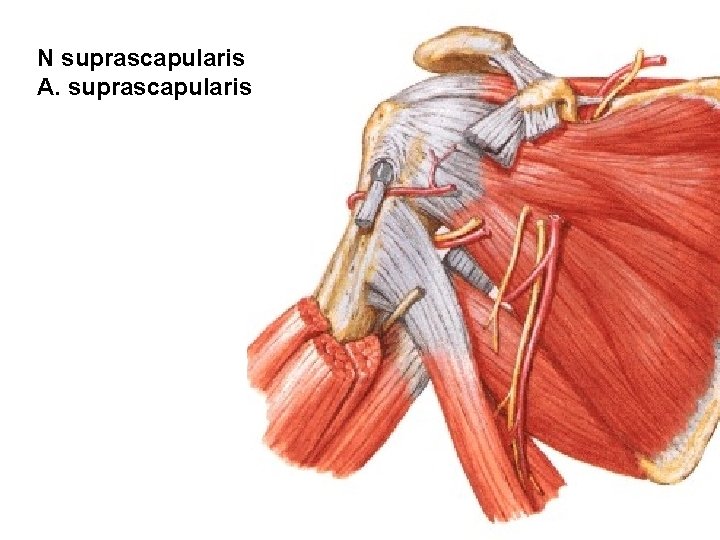

PARS SUPRACLAVICULARIS N. dorsalis scapulae (C 4, C 5) - mm. rhomboidei - m. levator scapulae N. thoracicus longus (C 5, C 6, C 7) - m. serratus ant. N. subclavius (C 5, C 6) - m. subclavius - art. sternoclavicularis N. suprascapularis (C 5, C 6) Rr. musculares - mm. scaleni - m. longus colli

N suprascapularis A. suprascapularis